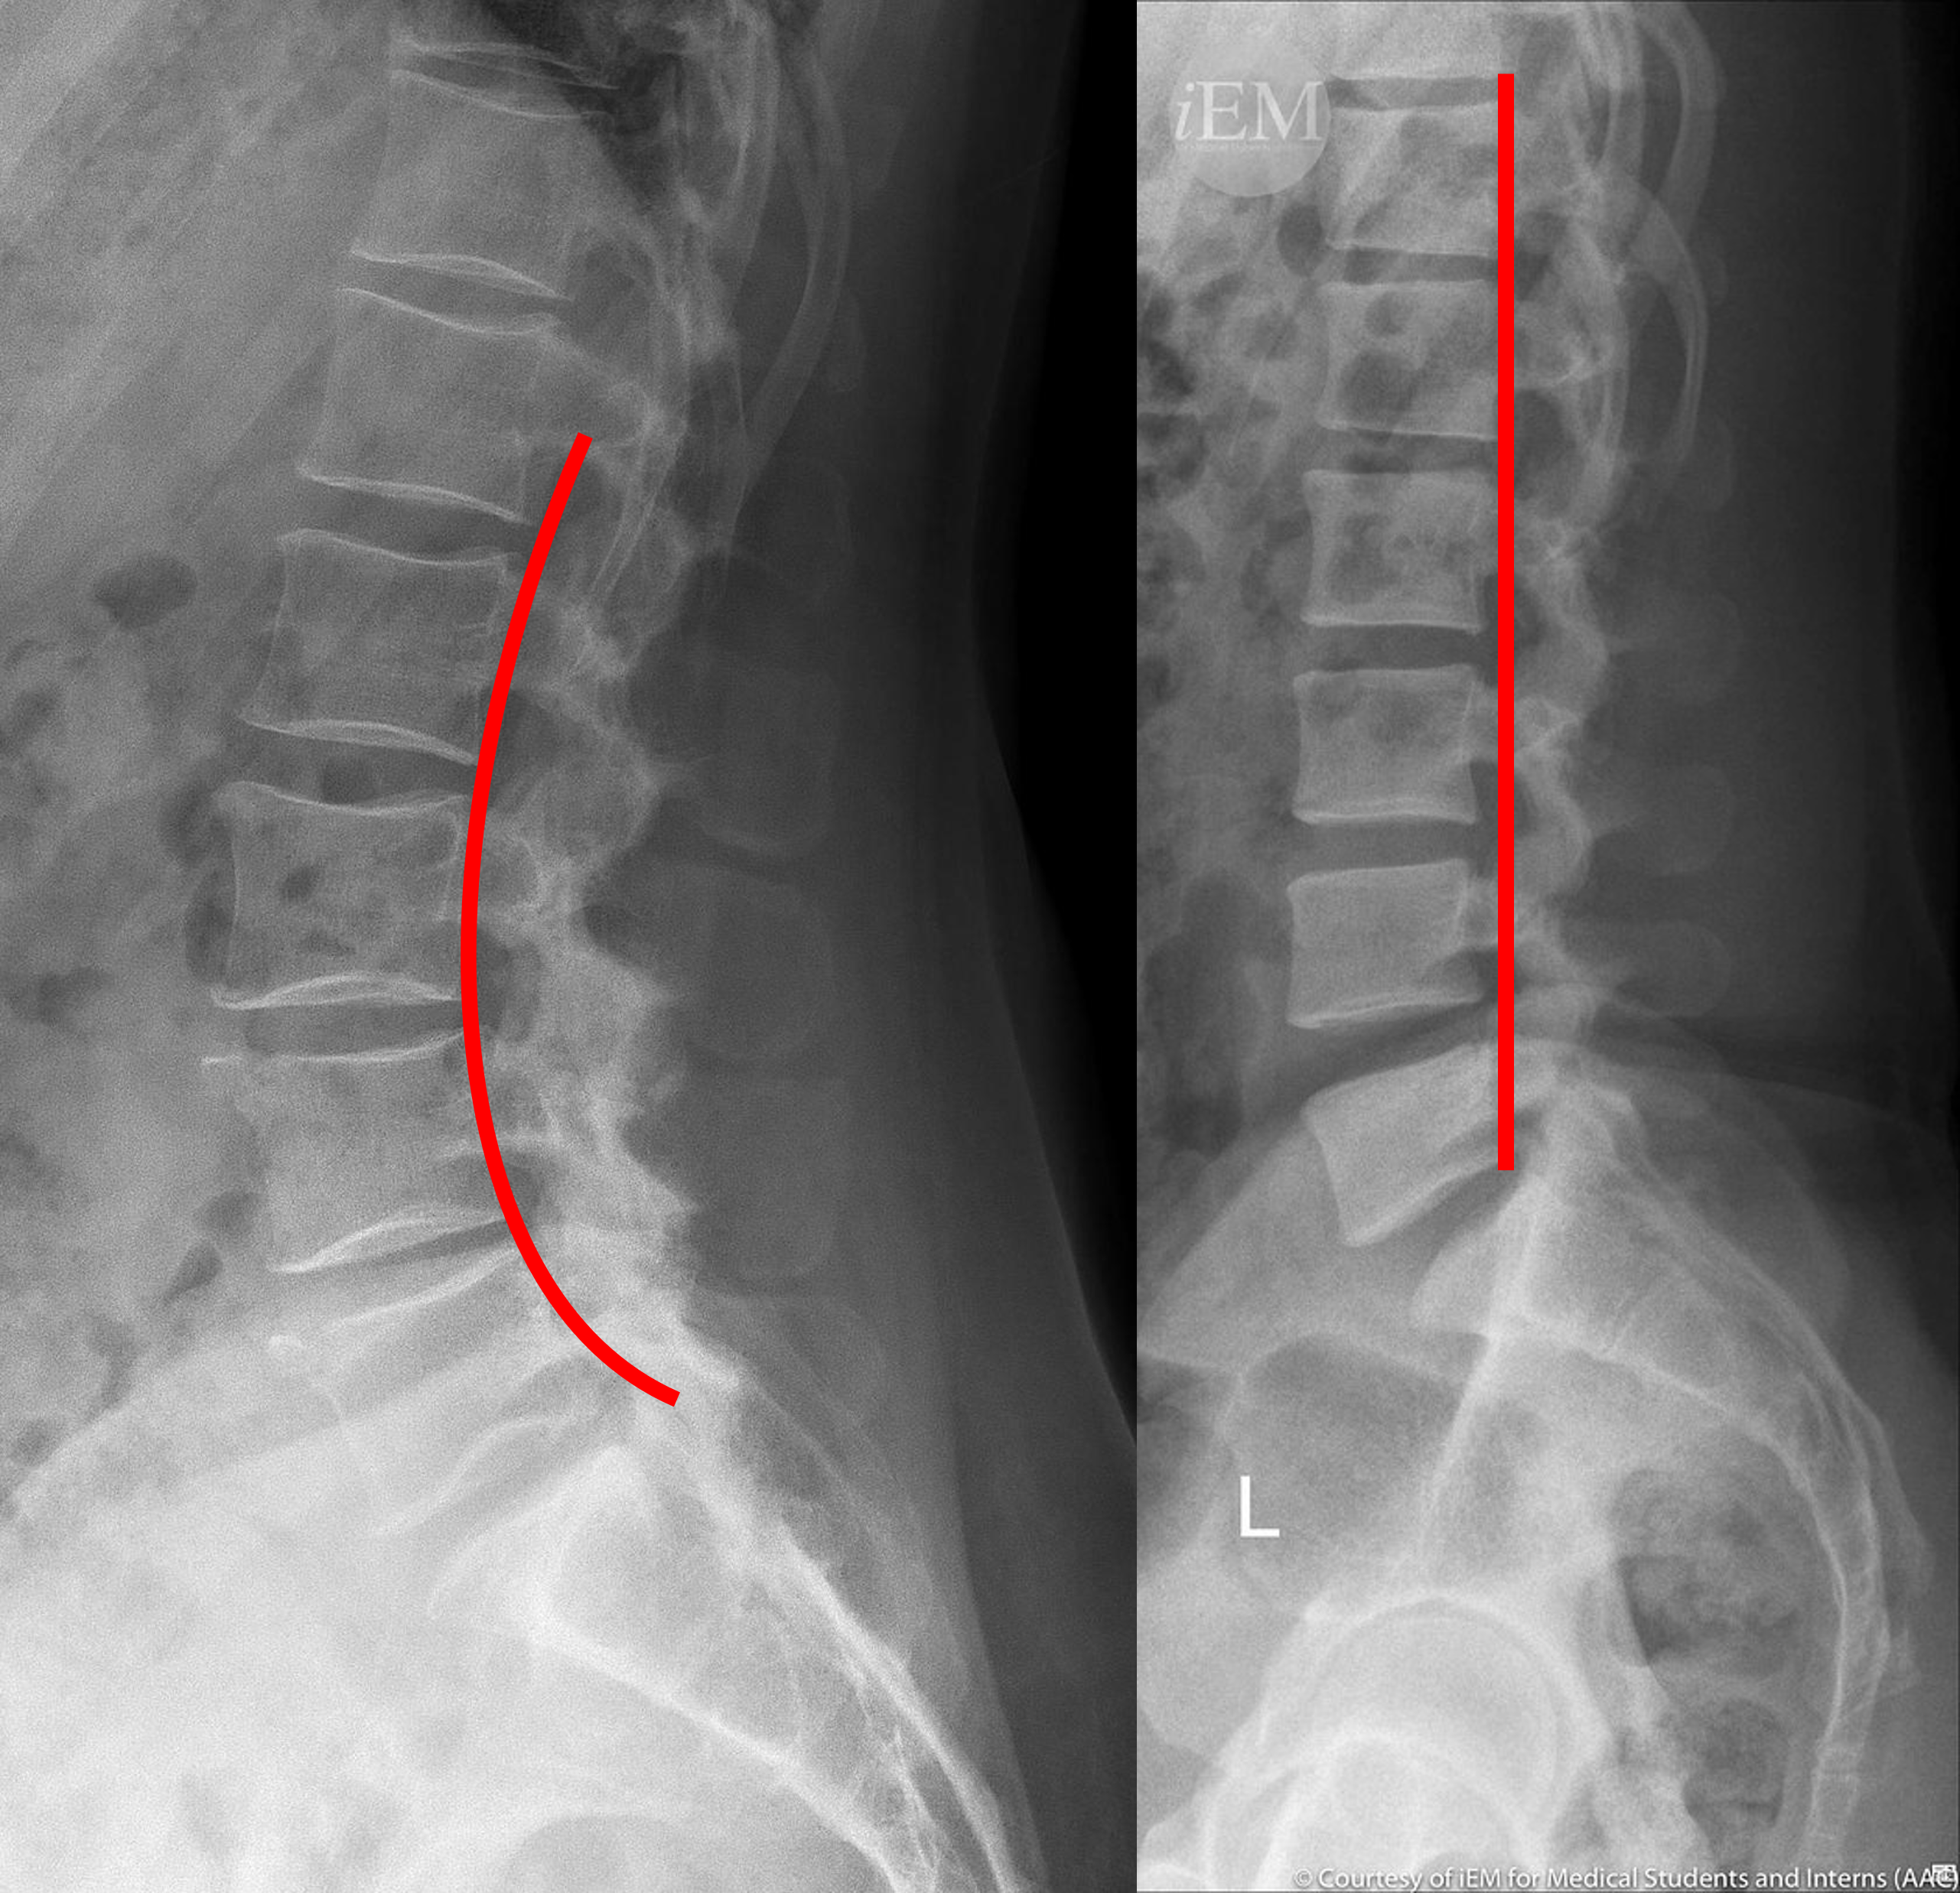

급성 허리 통증에서 X-ray로 확진을 하는 것은 상당히 제한됩니다. 일반적으로 허리 통증이 발생하게되면 척추를 양쪽에서 잡아주고있는 기립근과 같은 코어근육들이 긴장을 하기때문에, 원래는 C자형으로 만곡을 그리고 있어야할 요추가 반듯하게 펴진 듯한 소견을 관찰 할 수 있게 됩니다.

이러한 소견은 염좌에 관한 간접적인 소견에 해당하는데요, 그렇다면 좀 더 심각한 질병을 감별할 수 있는 소견은 무엇일까요? 디스크는 맨 처음 모식도 그림에서 보신 것처럼 척추 뼈 사이사이를 메꾸고 있는 콜라겐 조직입니다. 디스크의 손상은 결국 이러한 콜라겐 조직의 퇴행성 변화를 야기하게 되고, 그 결과 만성 디스크 환자의 경우 손상된 디스크의 높이가, 정상적인 디스크의 높이보다 낮아지게 됩니다.

또한 디스크의 기능 중 하나인 '관절의 안정성'이 무너지기 때문에, 망가진 디스크와 인접한 두 척추 뼈가 불안정하게 흔들리게되고, 이를 보상하기 위해 뼈가 자라나며 두 뼈 사이를 이어주려고 하는, 골극 형성이 일어나는 것도 확인 할 수 있습니다.